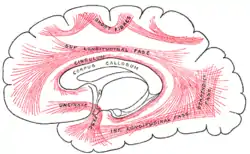

Diagrama mostrando os principais sistemas de fibras de associação no cérebro. | |

Dissecção do córtex cerebral e do tronco cerebral mostrando as fibras de associação e o córtex insular após a remoção de sua substância cinzenta superficial. | |

As fibras de associação unem diferentes partes do mesmo hemisfério cerebral e são categorizadas em dois tipos: (1) fibras curtas que conectam giros adjacentes; (2) fibras longas que fazem conexões entre partes mais distantes.[2]

Muitas das fibras curtas de associação (também chamadas de fibras arqueadas ou "U") ficam imediatamente abaixo da substância cinzenta do córtex dos hemisférios e conectam-se aos giros adjacentes.[2] Algumas ultrapassam de uma parede do sulco para a outra.[2]

As fibras longas de associação conectam os giros mais amplamente separados e são agrupadas em feixes,[2] incluindo as seguintes: